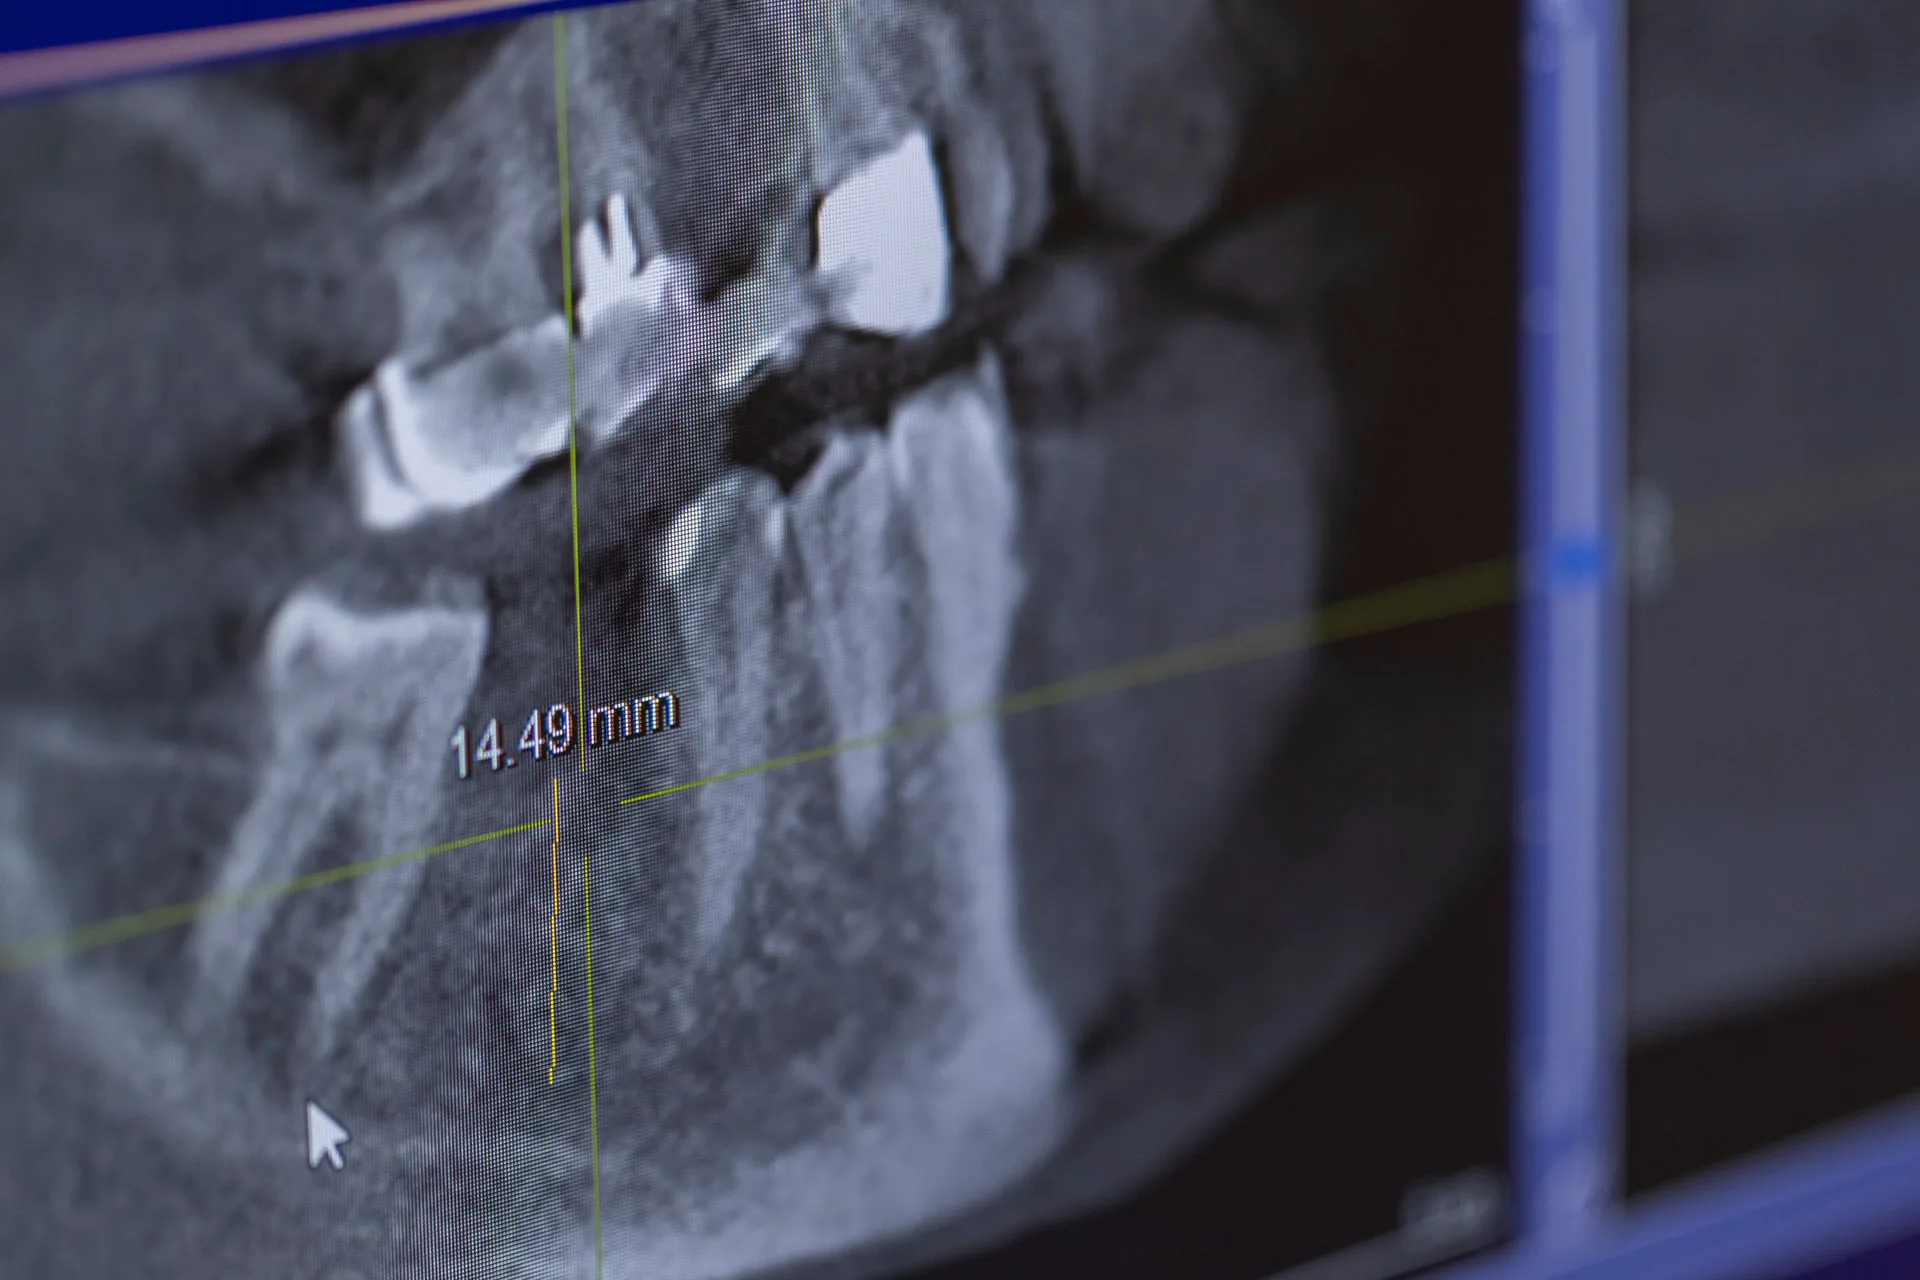

In unserer Praxisklinik steht die dentale Implantologie im Mittelpunkt. Mit über 500 erfolgreich

durchgeführten Implantationen pro Jahr gehört sie zu unserer täglichen Routine. Diese Erfahrung gibt

unseren Patienten die Sicherheit, von bewährten Techniken und höchster Präzision zu profitieren.

Dank modernster navigierter Implantologie bieten wir schonende Verfahren, die Funktionalität mit

höchster Ästhetik verbinden. Selbst komplexe Knochenaufbauten sind in der Regel ohne aufwendige

Knochenentnahmen möglich.